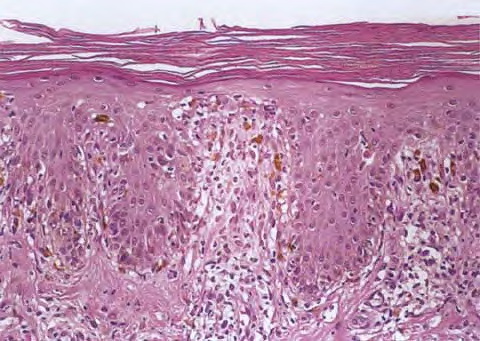

Atlas of skin histopathology

Fixed Drug Eruption =الاندفاع الدوائي الثابت